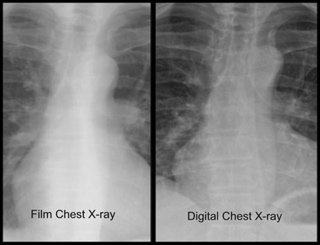

Computer software that enhances plain chest x-rays and identifies areas that need further work-up is now being tested in China and could be available in the United States in the next year or two.

The computer-aided detection (CAD) tool by Kodak was designed to improve lung cancer screening.

According to David Faller, general manager of CAD Business in Kodak’s Health Group, the only affordable way to test large populations for lung cancer at the current time is by chest x-ray, which can miss small or difficult to find lesions behind ribs.

Faller said Kodak’s new product enhances a normal x-ray in under a minute, allowing radiologists to see if there are “areas of interest” that require more extensive work-up. While there are other x-ray/CAD screening tools on the market, Faller said the Kodak system was faster, could be added to current equipment, and analyzes images in a way that allows radiologists to integrate the additional pictures into their normal workflow.

Caution; when ever you put a filter on any image you corrupt the fidelity (losing information) of the original image to highlight certain aspects. As long as the Radiologist looks closely at the original untouched image, along with the filtered image, then nothing is being missed. Filters never add information to an image, they only remove or modify image information.

That one or two pixels the filter removes/modifies can be the beginnings of a cancer.